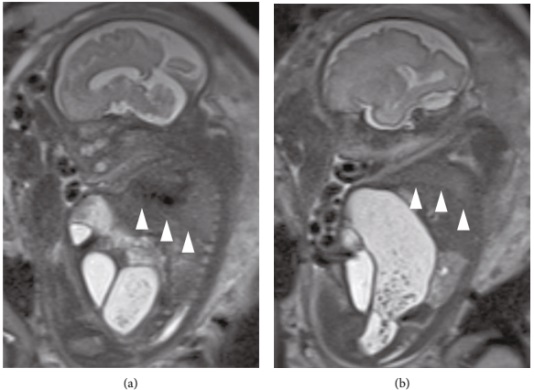

进行超声检查以对胎儿健康状况进行评估,包括大脑中动脉、脐带动脉和静脉导管的多普勒速度测定,以及生物物理分析,结果均正常。在妊娠30周时进行磁共振成像以评估肺发育,提示可能存在肺发育不全(图2)。妊娠32周时,尽管胎儿膀胱已充盈,但羊水过少持续存在,没有任何胎膜早破、胎盘功能不全、输尿管积水及肾积水的迹象。再加上肠扩张使胎儿腹部膨胀,胎儿尿道狭窄/梗阻,被认为引发了尿液从膀胱通过瘘管流向结肠。由于羊水过少和肠道扩张的恶化导致胸部压迫,最终导致进行性肺发育不全,预测期待治疗会恶化胎儿的预后。因此,产前给予糖皮质激素治疗,并在妊娠32周零5天时剖腹产分娩男婴。

图2. 胎儿MRI。妊娠30周,胎儿T2加权磁共振成像显示小肠扩张、羊水过少和肺发育不全。箭头表示膈膜